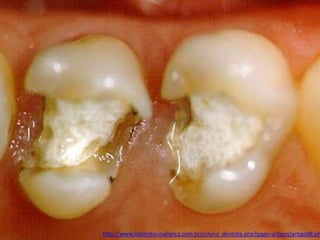

• Os dentes submetidos a tratamento endodôntido

precisam ter a câmara pulpar hermeticamente

vedada tanto entre as sessões quanto após o

término do procedimento. (PINHEIRO et al.,

1997; PECORA, 2002).

patrickbaltieri.blogspot.com.br/2011/08/procedimentos-pre-restauradores.html